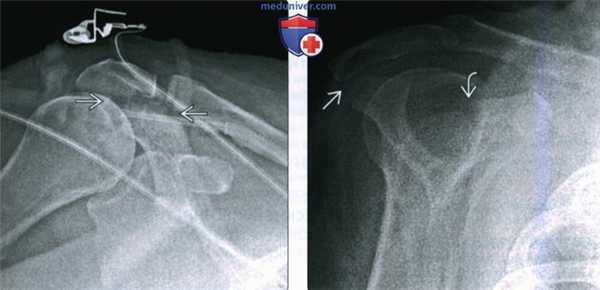

(Слева) На передне-задней рентгенограмме у пациента после ДТП определяется просветление в основании акромиального отростка, соответствующее перелому.

(Справа) На лопаточной Y рентгенограмме у этого же пациента подтверждается просветление в области соединения акромиального отростка и ости лопатки. Большинство переломов акромиального отростка можно вылечить консервативно. Кроме того, имеется просветление в основании клювовидного отростка. Пациент не мог принять положение для аксиллярной проекции, поэтому была выполнена КТ.

(Справа) На передне-задней рентгенограмме виден пациент со сглаженным плечевым суставом после ДТП. Имеется вколоченный перелом шейки лопатки и средней трети ключицы, соответствующий травме при плавающем плечевом суставе.